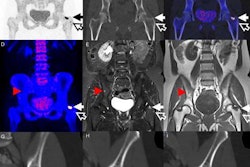

The prospective study included 50 women and one man with breast cancer (mean age of 56 years; range, 32 to 76 years; male age, 70 years) who completed PET/MRI with diffusion-weighted MRI (DWI-MRI) and PET/CT between July 2012 and October 2013. PET/CT scans were scheduled for various reasons, including evaluation after chemotherapy, monitoring distant metastases, and initial staging (Radiology, October 2016, Vol. 281:1, pp. 193-202).

PET/CT scans (Biograph mCT, Siemens Healthineers) were performed approximately 45 minutes after intravenous injection of FDG (mean dose, 547.6 MBq; range, 485 to 566 MBq) from the vertex to the thighs for 24 patients, or from the skull base to the thighs (due to an error in protocol) in 27 patients.

PET/MR images were acquired simultaneously with a PET/MRI scanner at 3 tesla (Biograph mMR, Siemens) a mean of 167 minutes (± 36 minutes) after FDG injection for PET/CT. Scans were conducted from the thighs to the vertex with the patient in the supine position, using a dedicated multichannel head and neck coil and a set of flexible body matrix coils.

Through the scans, the researchers found 242 distant metastatic lesions in 30 patients, 18 breast cancers in 17 patients, and 19 axillary nodes with positive findings in eight patients. Thirteen patients had no evidence of primary or metastatic disease.

In detecting distant metastases in the liver, PET/MRI had greater sensitivity than PET/CT. The researchers credited DWI-MRI in finding up to 40 liver metastases, compared with 28 liver metastases with PET/CT.

PET/MRI also achieved greater detection of bone lesions, with a combined 207 lesions for both readers, compared with a total of 196 lesions with PET/CT for both readers. In the comparison of lung metastases, both readers tallied a total of 55 true-positive results with PET/CT, compared with 37 true-positive findings with PET/MRI.

Axial PET/MRI (a-c) and PET/CT (d) images are from a 64-year-old woman with a history of left breast cancer metastatic to lung and bone. Images were obtained to monitor response during chemotherapy. A liver metastasis (arrow) is seen on PET/MRI (a-c), but not on PET/CT (d). The metastasis is best seen on the diffusion-weighted MR image (a), with corresponding low signal intensity on the apparent diffusion coefficient map (b). There is minimal corresponding FDG uptake on the fused diffusion-weighted and PET image (c). The metastasis is not seen on PET/CT images (d). Images courtesy of Radiology.In addition, the readers found 15 and 14 brain metastases, respectively, in five (10%) of the 51 subjects with PET/MRI. PET/CT found no brain metastases. The number of brain metastases came as a surprise to Melsaether and colleagues.